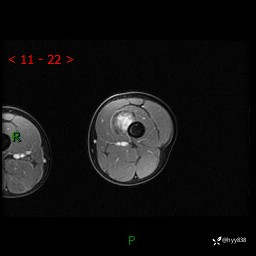

左大腿MRI平扫+增强